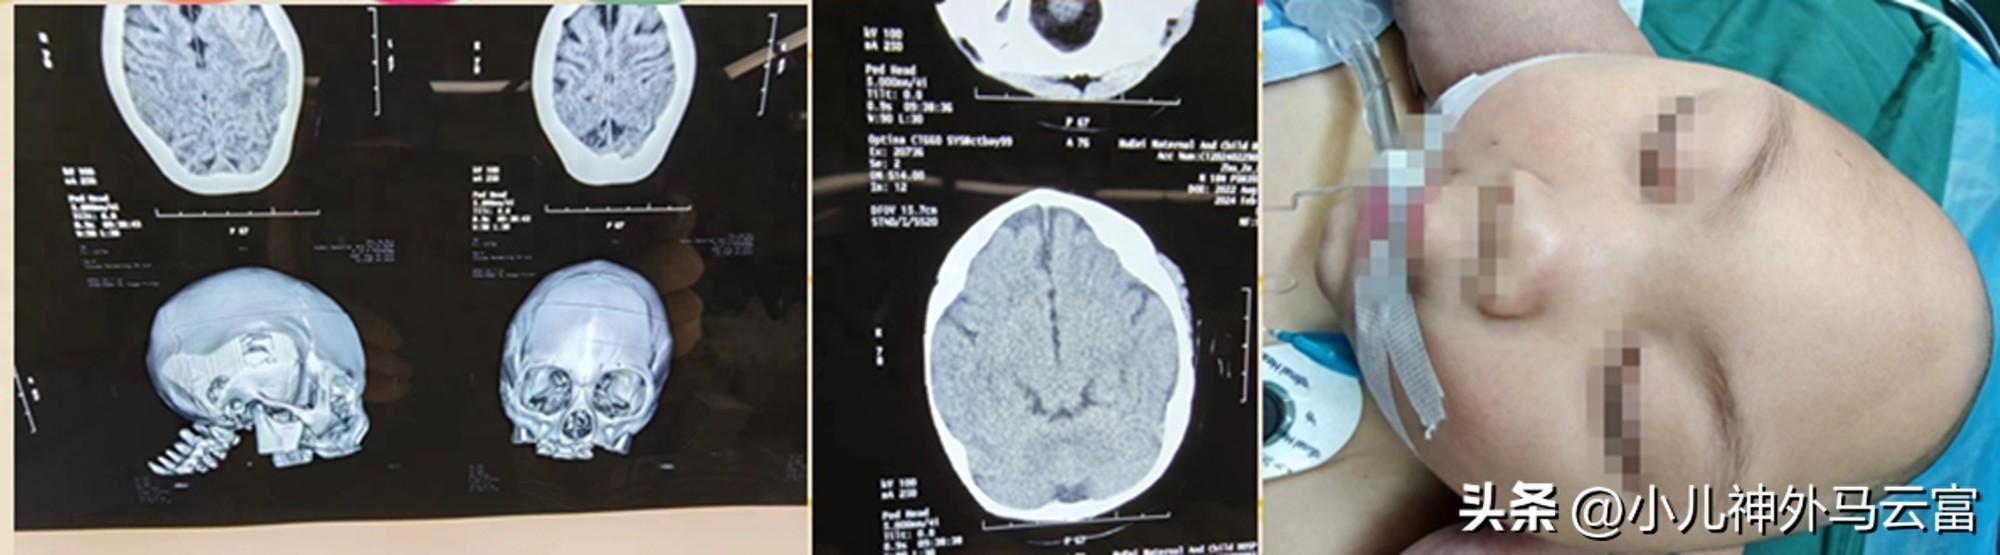

頭頂部小而尖,額頭扁平,頭圍比胸圍小,頭圍範圍僅40釐米,額與枕部常平坦。出生僅9個月的女嬰小麗(化名)患有嚴重的小頭畸形,外表看起來像外星人,在當地醫院無法治療的情況下,近日被送到湖北省婦幼保健院小兒神經外科求診。

4月11日,小麗的手術獲得成功,腦袋恢復情況很好,外表呈圓潤飽滿狀,五官也較術前端正可愛。在此次治療過程中,醫學專家由於在術前運用了3D打印技術,等比還原患兒顱骨,使得術中手術更具精確性、減少出血風險等,並且使重塑後的面容更具家族特徵。

馬雲富教授介紹,手術有兩個重要的目的:一是要把患者畸形的顱骨全部拆卸,鬆解被壓迫的大腦;二是對顱骨進行分割,逐個塑成需要的形狀,再重新拼接,這個過程就像玩拼圖一樣。然而,手術不僅需要技術,還要有立體裁剪的藝術美感,對於這個不到1週歲的孩子來說風險很大,也可能存在出血的可能。因此,手術前考慮採用3D建模的形式等比例還原患兒頭骨,在模型上預先設定裁剪方案、手術切割線等,確保“精準手術”,馬雲富教授表示,現在3D打印技術的出現,術前就按1:1的比例重現了小琳畸形的頭骨,3D建模成功後,一邊在腦中想像着裁剪方案,一邊在這個立體的、真實的頭骨模型上畫下了手術切割線。“實物模型不僅爲手術方案提供精準指南,還可以通過提前測量父母面部數據,爲患兒塑形後的面容體現父母特徵提供依據。”